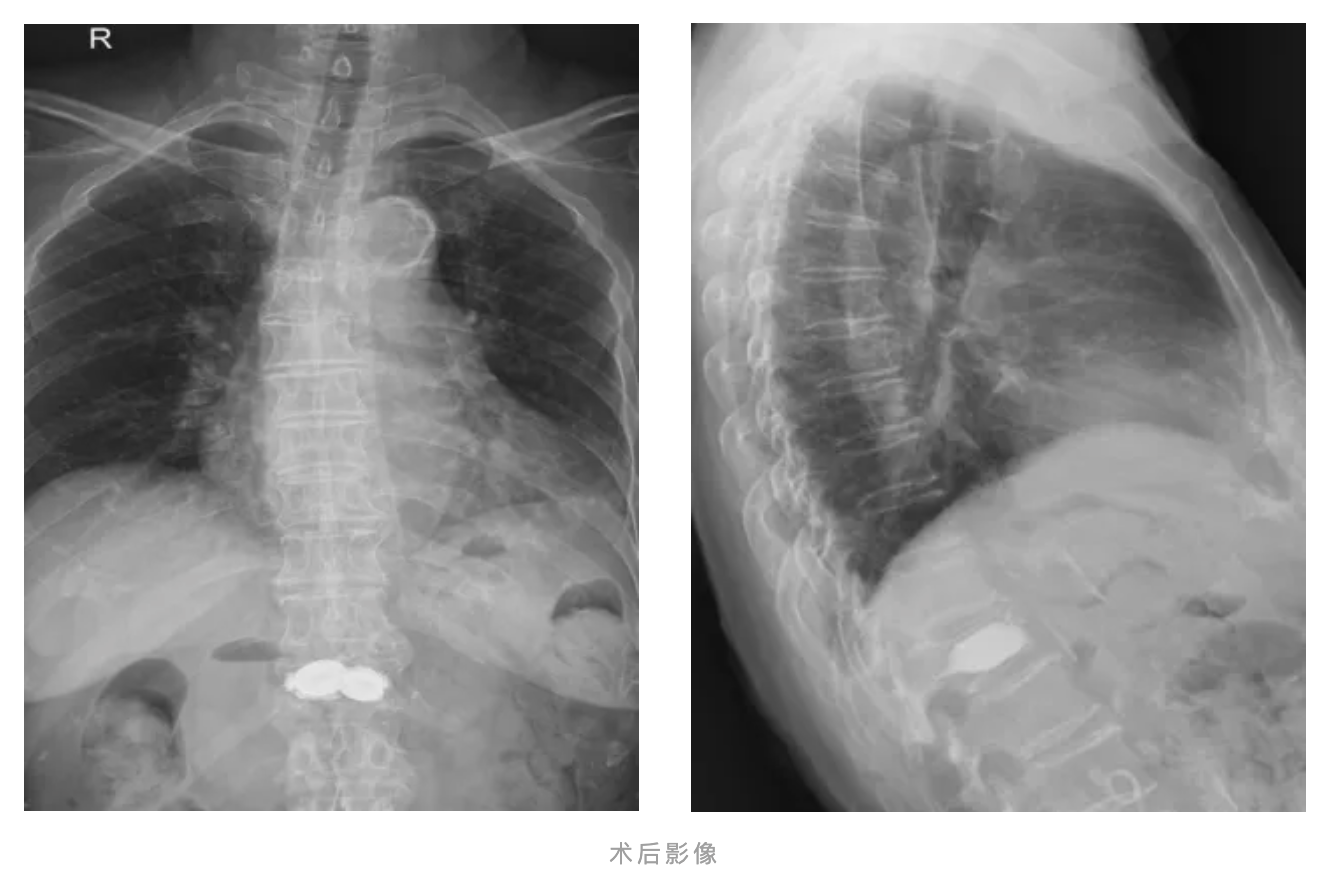

经皮椎体后凸成形术(PKP):在影像引导下,向压缩的椎体内放置钛网、注入骨水泥,快速稳定骨折部位,恢复椎体高度,进而实现缓解疼痛。PKP有创伤小、恢复好的特点,特别针对李奶奶这类高龄体弱合并其他疾病患者。

术后2小时,团队依据快速康复理念,指导李奶奶正确佩戴支具进行早期下床活动,恢复进程显著加快,术后第2天便可以独立行走,顺利出院。